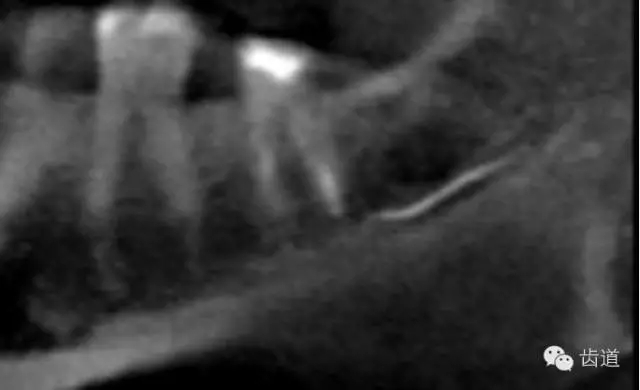

左下7根充后下唇麻木

左下5根管預(yù)備后下唇麻木

1.作根管治療前拍X線片,下頜牙齒應(yīng)特別注意與下頜管的關(guān)系。

2.準(zhǔn)確測(cè)量根管工作長(zhǎng)度,各種操作均在工作長(zhǎng)度范圍內(nèi)進(jìn)行。根管封藥不可過(guò)飽和,防止藥液溢出根尖孔。